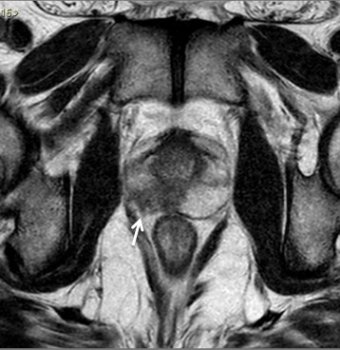

No estadiamento locorregional do câncer de próstata, o aspecto mais relevante na tomada de decisão terapêutica é a diferenciação entre tumor confinado ao órgão (T1 e T2) e tumor localmente avançado, sob as formas de extensão extraprostática (T3a) ou invasão de vesículas seminais (T3b). Para esta avaliação, as imagens ponderadas em T2 são as mais indicadas15,18

Os critérios de imagem para extensão extra-prostática incluem assimetria ou envolvimento macroscópico dos feixes neurovasculares, abaulamento, espiculação ou irregularidades da cápsula prostática, extensão direta para a gordura periprostática. Lesões que exibem contato maior que 1,0 cm com a cápsula prostática apresentam maior risco de extensão extracapsular.15,18

Os achados que indicam invasão das vesículas seminais incluem: aumento de tamanho, assimetria e hipointensidade das vesículas seminais, obliteração do ângulo vesicoprostático e extensão direta da base prostática à vesícula seminal, sendo este achado o de maior valor preditivo positivo.15,18 (fig. 5 e 6).

Figura 5. Estadiamento de adenocarcinoma de próstata Gleason 7. Imagem ponderada em T2 evidencia nódulo no terço médio da zona periférica direita, notando-se pequena irregularidade da cápsula prostática adjacente à lesão, sugestivo de extensão extra-prostática.